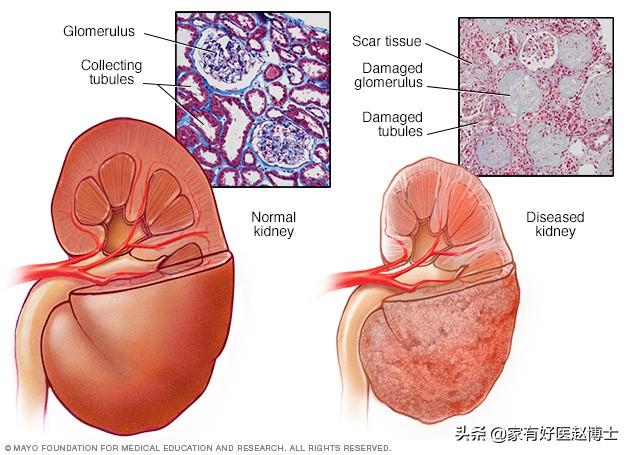

Pourquoi la microalbuminurie est-elle la première atteinte rénale de l'hypertension ? Le glomérule du rein étant en fait un ballon vasculaire, le sang de l'ensemble du corps est filtré par le glomérule pour produire l'urine. Lorsque le glomérule filtre l'urine, il y a une membrane de filtration et, dans des circonstances normales, des substances telles que les protéines ne peuvent pas être filtrées. En cas d'hypertension artérielle, l'augmentation de la pression artérielle endommage les vaisseaux sanguins et, bien sûr, les glomérules, de sorte que la membrane de filtration est endommagée et que les protéines s'échappent. Au début, il s'agit d'albumine de petit poids moléculaire, mais lorsque les dommages sont importants, des protéines de grande taille s'échappent également. Lorsqu'une plus grande quantité de protéines s'échappe, une protéinurie importante se produit et les analyses d'urine de routine révèlent la présence de protéines.

La relation entre l'hypertension et les reins est à la fois étroite et complexe, et les dommages causés aux reins par l'hypertension comprennent principalement : ① la néphrosclérose : au début de l'évolution des patients atteints d'hypertension essentielle légère et modérée, pendant une période assez longue, il n'y a pas de changements structurels et fonctionnels évidents au niveau des reins, seulement le spasme des petites artères rénales et l'affaiblissement de la fonction d'autorégulation rénale, comme la réduction de la capacité d'adaptation à des états non physiologiques tels qu'une charge élevée en sodium et une expansion volumique aiguë. Après un certain temps, en raison du spasme continu des petites artères rénales, celles-ci subissent une dégénérescence, un durcissement et un rétrécissement, et les unités rénales subissent une atrophie et une sclérose dues à l'ischémie, ce qui nuit gravement à la fonction rénale. L'hypertension primaire se manifeste d'abord par des lésions des tubules rénaux et des changements fonctionnels, le patient se manifeste par une nycturie accrue, les tests de laboratoire révèlent une petite quantité de protéines dans l'urine, principalement des protéines à petites molécules (la β2 microglobuline est un trait caractéristique), la gravité spécifique de l'urine est réduite et la capacité d'acidification de l'urine est diminuée. En général, l'hypertension primaire continue à se développer régulièrement et une petite artériosclérose rénale légère à modérée peut apparaître après 5 à 10 ans. ② athérosclérose de l'artère rénale : l'hypertension est un facteur causal important de l'athérosclérose, et l'artère rénale est un site privilégié de l'athérosclérose. L'artériosclérose rénale réduit le flux sanguin rénal, active le système rénine-angiotensine-aldostérone, provoquant une vasoconstriction, une rétention de sodium et une nouvelle élévation de la pression artérielle, formant ainsi un cercle vicieux. Environ 7 % des patients atteints d'hypertension primaire présentent une augmentation soudaine et progressive de la pression artérielle au cours de la maladie, qui se transforme en hypertension maligne. Lorsque la pression artérielle évolue vers une hypertension aiguë, une nécrose fibrinoïde des petites artères rénales se produit, et les reins sont gravement ischémiés, avec une détérioration rapide de la fonction rénale et une progression rapide vers l'urémie.

- Les reins sont constitués de glomérules et de tubules. Les glomérules sont comme un tamis qui élimine les déchets dont l'organisme ne veut pas et conserve les protéines dont l'organisme a besoin. L'urine qui passe par le glomérule est appelée urine primaire. Le glomérule est un tamis grossier, et l'urine primaire contient de nombreuses autres substances dont l'organisme a besoin, comme de l'eau et du glucose au maximum, qui doivent être réabsorbées et réutilisées.

Les lésions rénales dites hypertensives sont, par définition, des lésions structurelles et fonctionnelles des reins dues à l'hypertension artérielle.

Normalement, l'albumine présente dans le sang ne traverse pas la barrière de filtration des reins et n'entre donc pas dans l'urine. Cependant, l'hypertension entraîne des modifications de l'hémodynamique rénale et la pression dans les capillaires des glomérules augmente, ce qui entraîne une augmentation de la filtration rénale. Il en résulte queUne manifestation précoce des lésions rénales dues à l'hypertension est un taux élevé de microalbumine dans l'urine.。

Normalement, les deux microglobulines peuvent passer à travers les glomérules dans les tubules rénaux, mais sont réabsorbées à l'extrémité proximale des tubules. Cependant, lorsque des lésions rénales hypertendues provoquent une fonction tubulaire anormale, la réabsorption tubulaire de ces deux microglobulines est réduite, ce qui entraîne une augmentation de leur taux dans l'urine. En d'autres termes.Lorsque ces deux indicateurs sont élevés dans l'urine, il est probable que les tubules des reins soient endommagés.。

L'hypertension artérielle peut également entraîner une atrophie des reins.

Les reins normaux sont ronds et pleins, et l'hypertension artérielle à long terme entraîne un rétrécissement des reins des patients, avec une surface granuleuse et une diminution de la fonction rénale.

Un choc prolongé d'hypertension artérielle entraîne, dès le début, une modification de la membrane filtrante mentionnée plus haut, c'est-à-dire une modification de la perméabilité, de sorte que certaines des plus grosses molécules, telles que l'albumine, qui ne pourraient autrement pas traverser la membrane filtrante, s'échappent de la membrane filtrante et que l'albumine puisse être détectée dans l'urine. Une pression artérielle plus élevée, pendant une période plus longue, agit sur les artères des reins, provoquant le rétrécissement de certaines des petites artères des reins, ce qui finit par réduire la quantité de sang qui atteint la membrane filtrante et, naturellement, la quantité d'urine produite sera également réduite, d'où une diminution de la quantité d'urine.